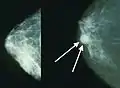

Elastography shows stiff cancer tissue on ultrasound imaging. Mammograms showing a normal breast (left) and a breast with cancer (right)

Mammograms showing a normal breast (left) and a breast with cancer (right)

Breast cancer screening refers to testing otherwise-healthy women for breast cancer in an attempt to diagnose breast tumors early when treatments are more successful. The most common screening test for breast cancer is low-dose X-ray imaging of the breast, called mammography.[113] Each breast is pressed between two plates and imaged. Tumors can appear unusually dense within the breast, distort the shape of surrounding tissue, or cause small dense flecks called microcalcifications.[114] Radiologists generally report mammogram results on a standardized scale – the six-point Breast Imaging-Reporting and Data System (BI-RADS) is the most common globally – where a higher number corresponds to a greater risk of a cancerous tumor.[115][116]

A mammogram also reveals breast density; dense breast tissue appears opaque on a mammogram and can obscure tumors.[117][118] BI-RADS categorizes breast density into four categories. Mammography can detect around 90% of breast tumors in the least dense breasts (called "fatty" breasts), but just 60% in the most dense breasts (called "extremely dense").[119] Women with particularly dense breasts can instead be screened by ultrasound, magnetic resonance imaging (MRI), or tomosynthesis, all of which more sensitively detect breast tumors.[120]